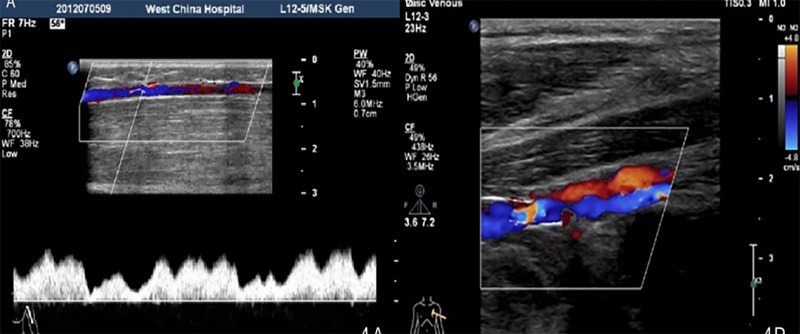

Klippel-Trenaunay综合征是一种罕见的先天性疾病,其特征是三种症状:毛细血管畸形、静脉异常、骨骼和软组织肥大。该综合征通常表现为葡萄酒色斑,静脉曲张和肢体肥大,可导致严重的并发症,如静脉血栓栓塞和出血。我们报告一例13岁的女性,出生后左上肢和肩部出现红斑。采用了一种有效的治疗方法,其中包括一个多学科的专家团队,专门从事皮肤病学和血管外科的各个领域,所有人都以患者的健康为核心进行合作。这种方法强调基于患者偏好的个性化策略。

Klippel-Trenaunay Syndrome is a rare congenital disorder characterized by a triad of symptoms-capillary malformations, venous abnormalities, and hypertrophy of bones and soft tissues. The syndrome often presents with port wine stains, varicose veins, and limb hypertrophy, which can lead to significant complications such as venous thromboembolism and bleeding. We present a case of a 13 ' year female, with erythema in left upper limb and shoulder since birth.. An effective treatment method was employed, which incorporated a multidisciplinary team of experts specialized in various fields of dermatology and vascular surgery, all working collaboratively with the patient's well-being at the core of their efforts. This approach emphasized a personalized strategy based on the patient's preferences.